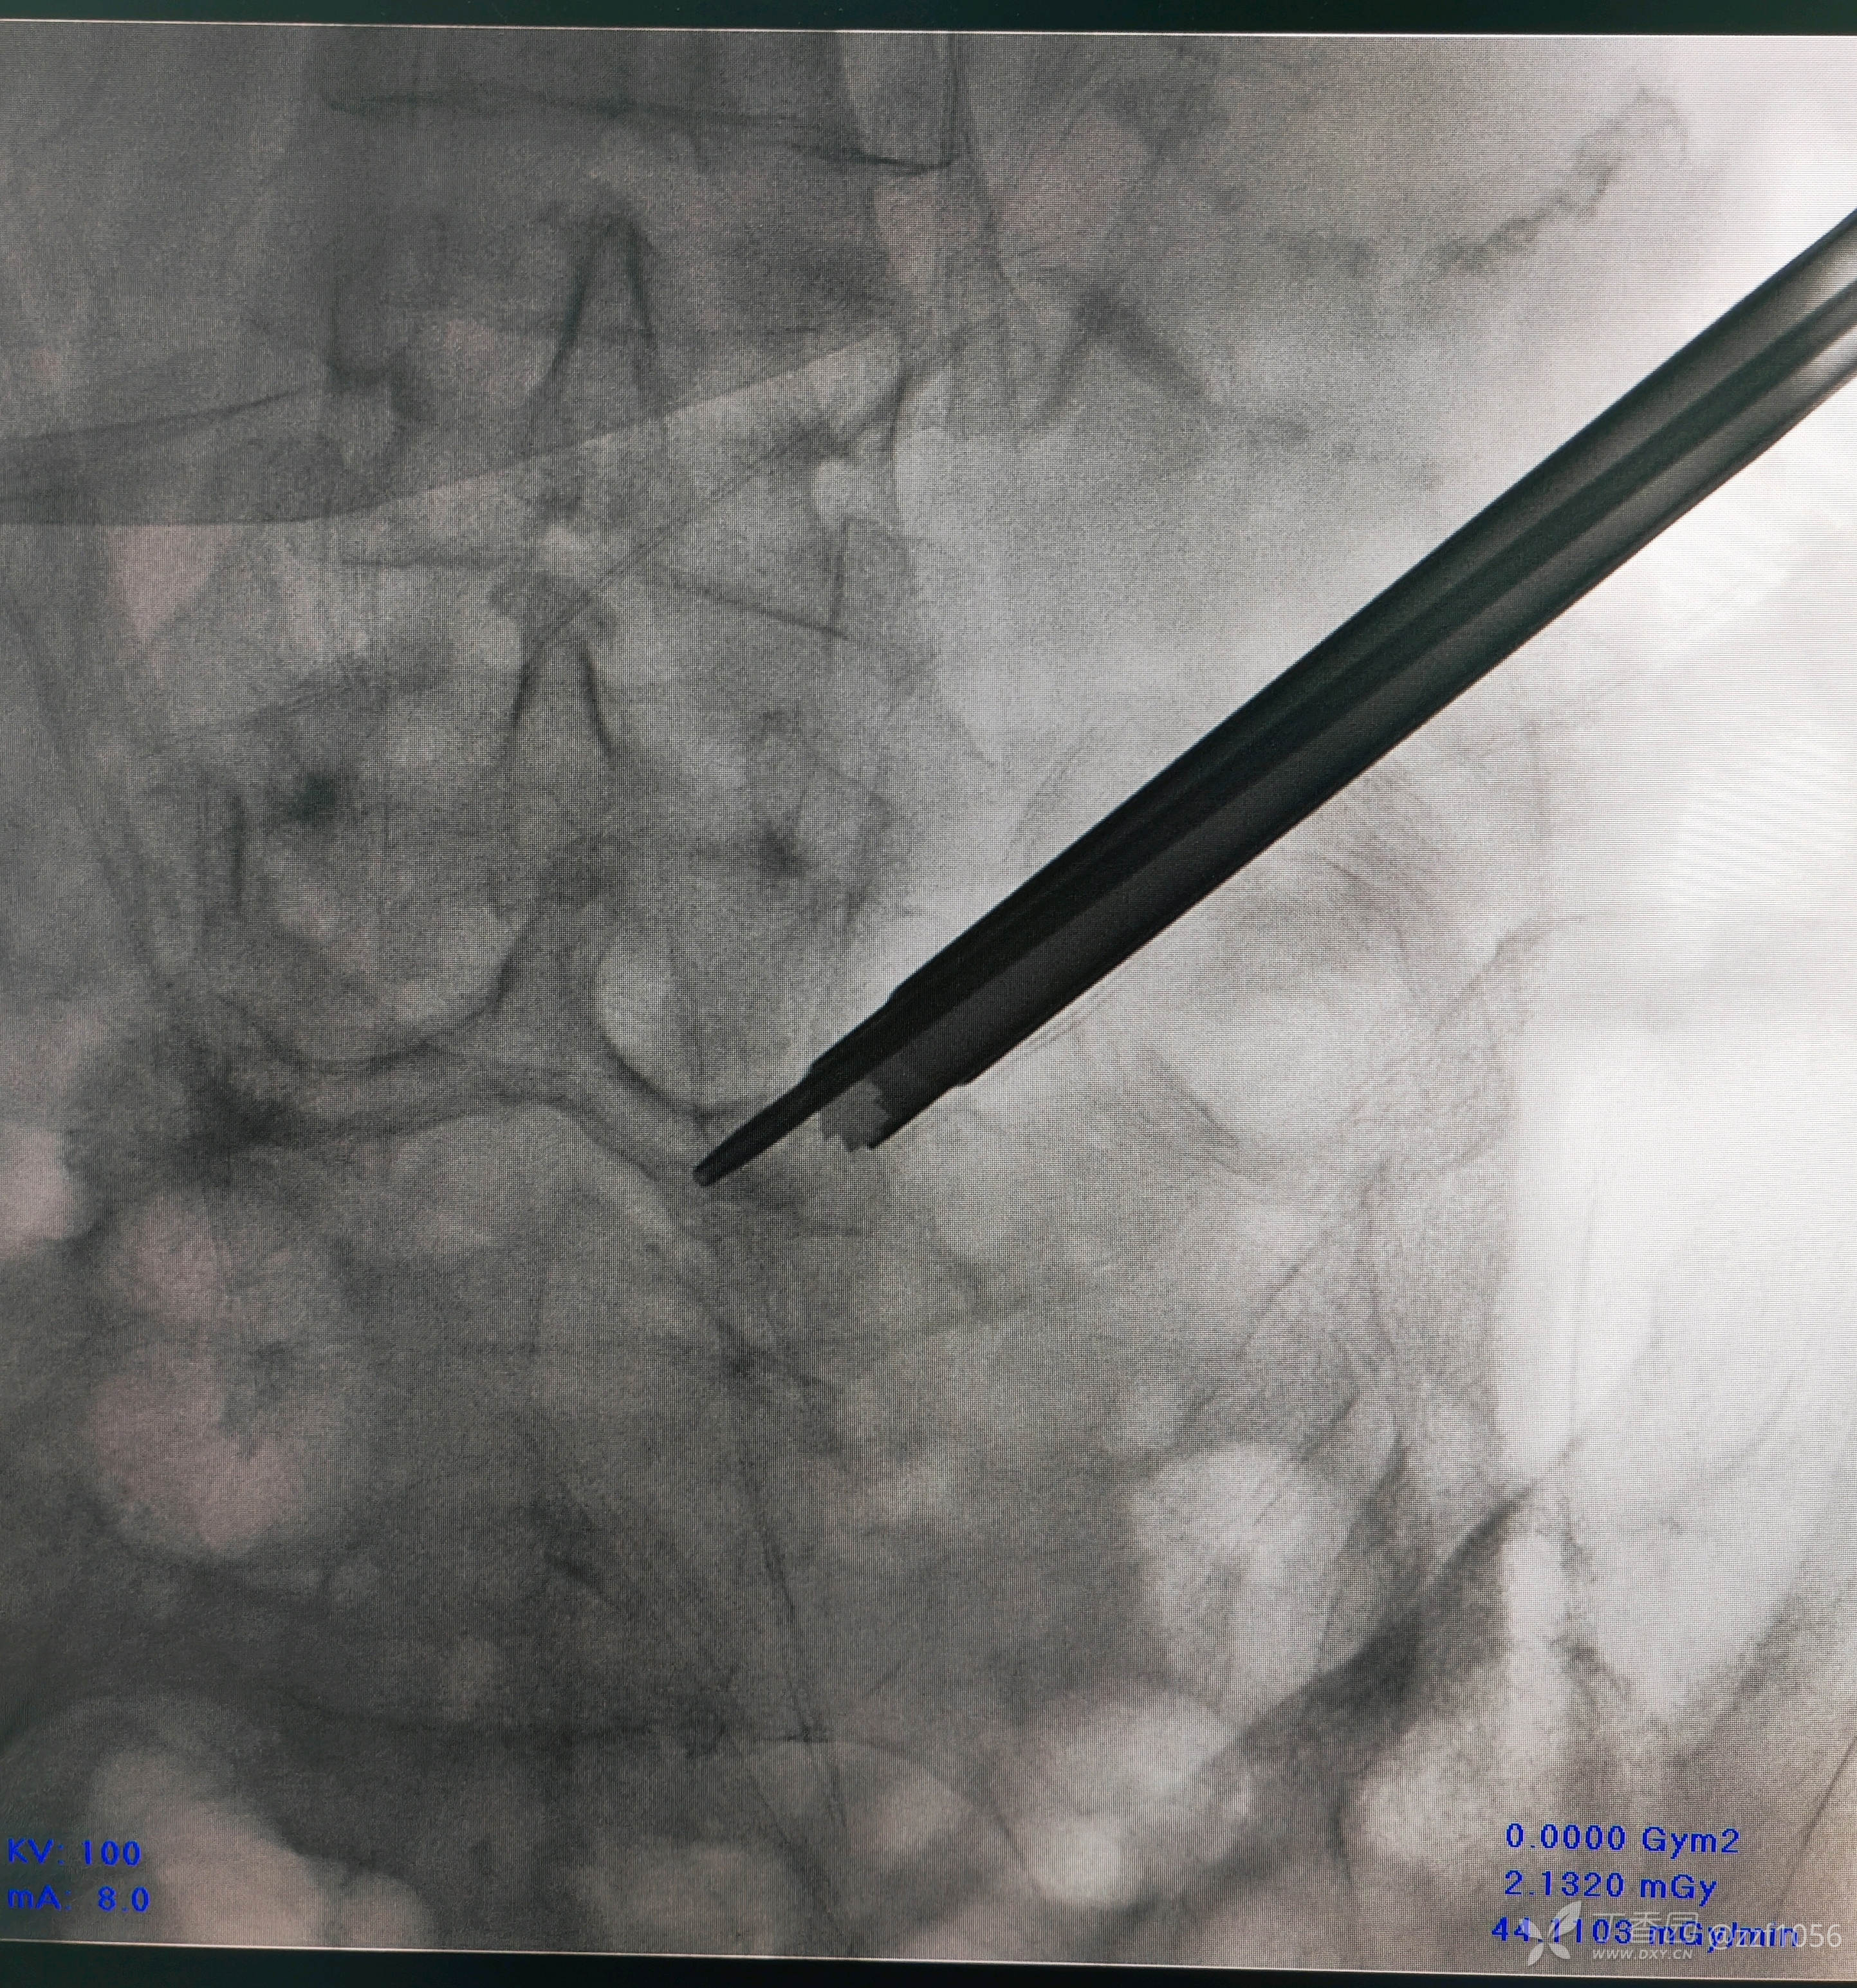

一级扩张管进盘内了

可视环锯椎间孔成型,黄韧带确实肥厚,够韧,髓核压迫明显

270°减压